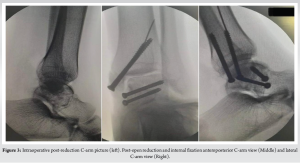

Case Report: We share this unusual case of a Hawkins type-3 talus neck fracture along with a serious Grade 3B medial malleolus fracture and ankle subluxation, which was treated with cleaning the wound, realigning the ankle, and surgery to fix the bones. Post-operatively, the wound was healthy and free of infection. Despite being told to avoid weight-bearing for three months, the patient lost follow-up after a month and started occasional partial weight bearing. During the 10th post-operative week, we found a mild degree of talar neck collapse and Hawkins sign radiologically. The range of motion for the ankle was dorsiflexion of 0–15° and plantar flexion of 0–30°, with minimal swelling and pain on weight bearing.

The combination of talar neck fracture and ankle subluxation, along with ipsilateral medial malleolar fracture, is exceptionally rare. Very few cases have been reported until now [4,5]. Numerous reports have been made of complications, such as osteonecrosis, collapse, malunion, post-traumatic arthritis, and discomfort [3]. The time of definitive fixation depends on multiple factors, including fracture comminution and subtalar dislocation/subluxation [6,7]. Talus fractures that happen with a malleolar fracture have a lower chance of avascular necrosis (AVN) because the ligament-capsule complex between the broken piece and malleolus is still intact, which helps keep the blood supply and soft tissue healthy. In our case, we operated on an emergency basis within 10 h of injury due to associated fracture comminution, open soft tissue injury, and unreduced ankle subluxation to minimize the risk of future avascular necrosis. A retained broken guide wire during medial malleolus fixation was decided not to remove given its harmless intramedullary position and to prevent the further soft tissue damage that will incur during the extraction process that will increase the overall operative time and chances of infection. Although asymptomatic, this intraoperative event underscores the need for caution during hardware placement and raises potential concerns for future procedures. Post-operative x-rays revealed a partial Hawkins sign in the central and medial region of the talar dome, which is reliable evidence of talus vascularity after fracture and suggests that the chances of AVN are unlikely [8,9]. Our case was managed without CT or MRI, which the patient declined given the patient’s poor socio-economic status. While this limited detailed fracture assessment, it emphasizes the role of clinical judgment and standard radiographs in urgent surgical decision-making when advanced imaging is unavailable. The present standard for treating talus neck fractures is to use the anteromedial and anterolateral dual incision techniques [6]. In our case, we used the open medial wound proximally and extended the incision anteromedially and distally. Open fractures, which are frequently accompanied by soft tissue contamination and stripping, were discovered to have a 25% deep infection risk in open talus injuries [10]. The emergency reduction of dislocation, limb elevation, appropriate antibiotic administration, and tension-free suturing of the wound can all help to reduce soft tissue and wound problems, such as skin necrosis, infections, and poor wound healing [6]. Our patient showed no signs of a superficial or deep surgical site infection after surgery. While the single anteromedial approach was effective in our case, further randomised comparative studies with standard dual-incision techniques will be required to study the relative benefits or limitations of this approach. Several studies [6] have found a correlation between poor functional results and increasing injury severity. Although our patient lost contact after a month and began intermittent partial weight-bearing, the patient had better functional results. Talar neck malunion rates can range from 20% to 37%, while talar neck nonunion rates are uncommon (5% each) [7]. On the X-ray taken in the 10th week following surgery, there was no sign of talar neck malunion in our case. Despite instructions for strict non-weight bearing, the patient began early partial weight bearing. This sub-optimal compliance is explained by the poor socioeconomic status, cultural belief, long travel distance from their rural area to the hospital etc. This introduces a variable in outcome interpretation and underscores the importance of understanting the patient’s socio-economic condition. Post-traumatic subtalar arthritis is a typical long-term complication in such cases [7]. Our case requires a long-term follow-up since post-traumatic arthritis progresses over time. Our patient discontinued follow-up after one month, returning only at the 10th week yet presented with good clinical and functional outcome given the complexity of the case presentation. This highlights the challenges of ensuring long-term monitoring in trauma cases, especially in socioeconomically constrained populations.